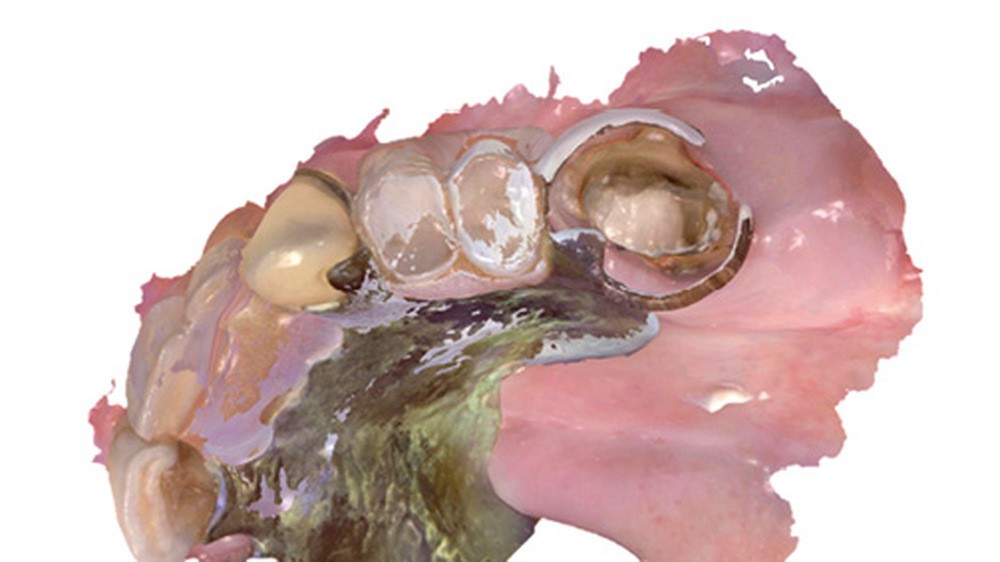

La corrélation de fichiers est un vrai facilitateur pour les plans de traitement prothétique ; que ce soit pour le suivi des cas, ou dans des cas particuliers comme celui de la couronne sous châssis. Cette situation est toujours préjudiciable pour le patient en empreinte conventionnelle, car elle oblige à priver ce dernier de sa prothèse adjointe le temps que le laboratoire conçoive la couronne. Avec l’empreinte optique, il suffit d’enregistrer le crochet et sa position par rapport à la préparation pour que le prothésiste puisse concevoir une prothèse adaptée à la cavité buccale et à la prothèse amovible. Autre cas particulier, lors de la réalisation d’inlay-core, les logiciels de laboratoire ont des algorithmes qui autorisent la conception en seul temps de l’inlay-core et de la couronne avec un calcul des morphologies des éléments pour qu’ils respectent à la fois l’homothétie et les épaisseurs minimales de matériau (fig. 3 et 4).